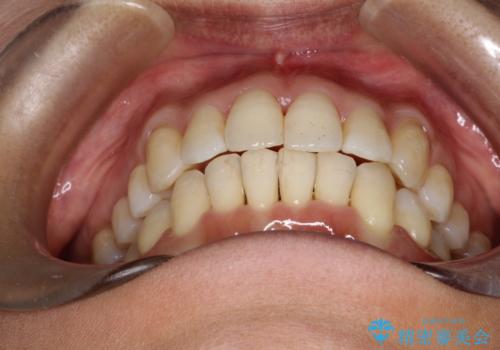

重度のガタガタのインビザラインによる非抜歯矯正

しっかりとマウスピースを使用していただけたので、順調に治療を終えることができました。

- 上下の歯のガタガタを主訴に来院されました。

インビザラインで奥歯を後方に移動させるのと、歯と歯の間をわずかに削ることでスペースを作り、歯を並べる計画としました。